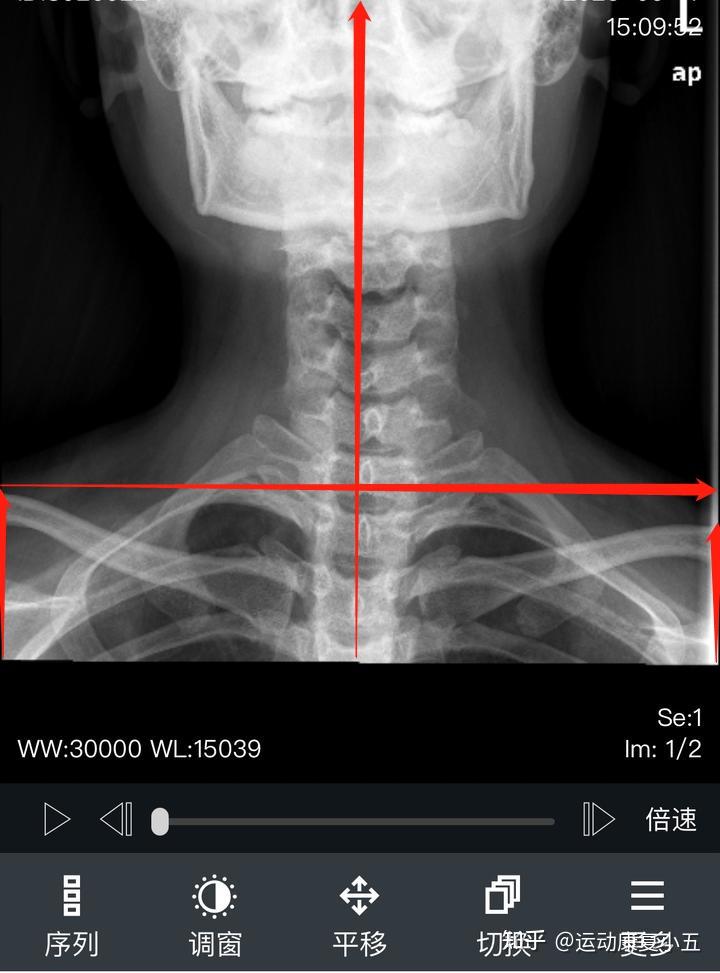

颈部x光片

图中为其颈椎正侧位x光片

请问有会看这颈部x光片吗?